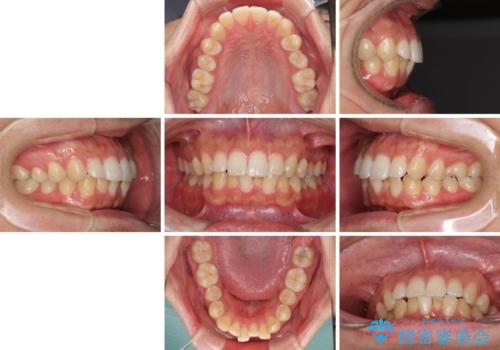

前歯のデコボコと突出感 インビザラインにて矯正治療

- 上下前歯のデコボコを気にして来院された患者様です。

インビザラインによる上下歯列の側方拡大と後方移動、IPR(歯と歯の間を削る)にるスペースの獲得により歯列を整えることとしました。

左上の小臼歯は捻転が強く、あえて180逆向きの状態で終了させる治療計画としました。

ご自宅と職場がともに遠方であったため、治療期間は長くなりましたが、患者様も我々も期待して以上に口元の突出感を改善することができました。